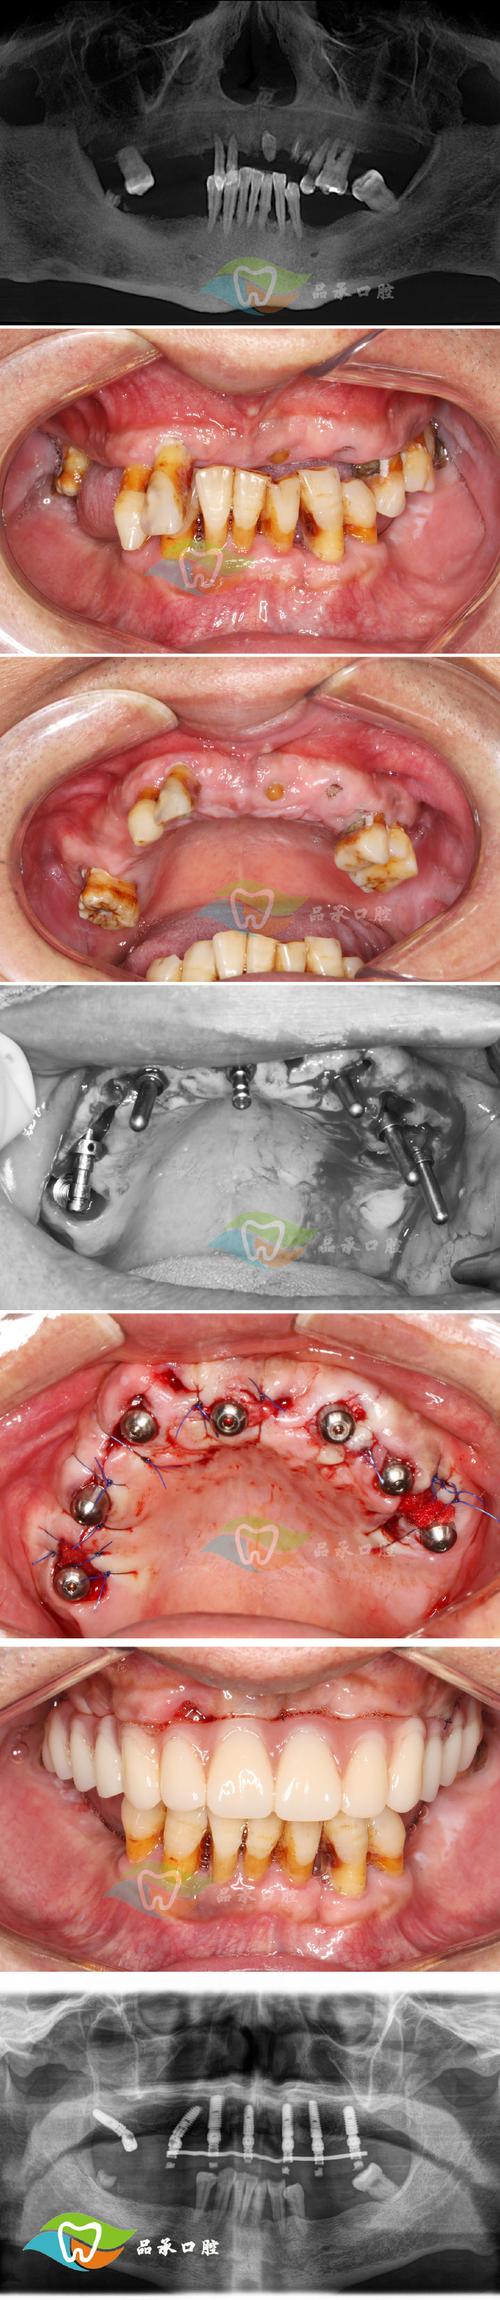

即刻负重植牙手术是一种在拔除患牙后,同期植入种植体,并在短时间内(通常为24小时内)安装临时修复体,实现即刻恢复部分咀嚼功能的种植牙技术,与传统种植牙需等待3-6个月骨结合期后再安装牙冠不同,即刻负重通过精准的术前规划、微创手术及高初期稳定性的种植体设计,大幅缩短了治疗周期,让患者更快恢复口腔功能与美观。

该技术的核心在于确保种植体在植入后具备足够的初期稳定性,这是即刻负重成功的关键,术前需通过CBCT影像评估牙槽骨的密度、高度及宽度,判断是否符合即刻负重的条件——通常要求牙槽骨无明显吸收、骨量充足(如骨密度达到Ⅲ类以上),且无严重牙周病、糖尿病等全身性疾病,手术过程中,医生会采用微创拔牙技术,最大限度保留牙槽骨,随后将经过表面处理(如喷砂酸蚀、亲水涂层)的种植体精准植入拔牙窝,确保种植体与骨面紧密贴合,初期稳定性达到理想值(如种植体动度<50μm),随后,医生会通过数字化印模或口内扫描,在当天或次日为患者安装临时牙冠,使患者即刻拥有接近天然牙的咀嚼能力。

即刻负重植牙手术的优势显著:治疗周期大幅缩短,传统种植需多次复诊等待骨结合,而即刻负重可能将总治疗时间压缩至数周内;减少就诊次数,尤其适合工作繁忙或异地患者;即刻恢复咀嚼功能,避免传统种植期间因缺牙导致的饮食受限、邻牙移位等问题;功能性刺激可延缓牙槽骨萎缩,维持口腔软组织形态,提升长期效果,但该技术并非适用于所有人群,需严格筛选适应症,对骨量不足、咬合力过大或口腔卫生不佳的患者,可能需先进行骨增量或改为延期负重。

为更直观理解,以下是即刻负重植牙手术的关键步骤及要点:

| 术前评估 | CBCT影像检查、口腔模型分析、全身健康状况筛查 | 判断骨量、骨质及全身条件是否符合即刻负重标准 |

| 微创拔牙 | 使用精细器械拔除患牙,尽量保留牙槽骨骨壁 | 避免骨损伤,为种植体提供良好植骨床 |

| 种植体植入 | 选择合适直径长度的种植体,精准植入拔牙窝 | 确保初期稳定性,植入扭矩通常达35N·cm以上 |

| 临时修复体安装 | 数字化印模或口内扫描,制作并安装临时牙冠 | 调整咬合,避免早接触,保护种植体不受过大侧向力 |

| 术后随访 | 定期复查(术后1周、1个月、3个月等) | 监测骨结合情况,临时牙使用3-6个月后更换为永久修复体 |